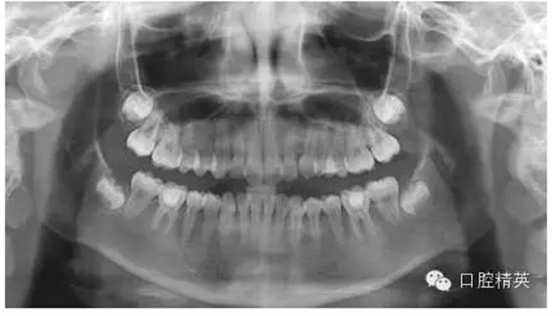

后來本診所求診,以下為取斷針的部分影像:

1,術(shù)前X-ray,常規(guī)術(shù)前攝片,

為患者和自己保留一份客觀記錄。。。